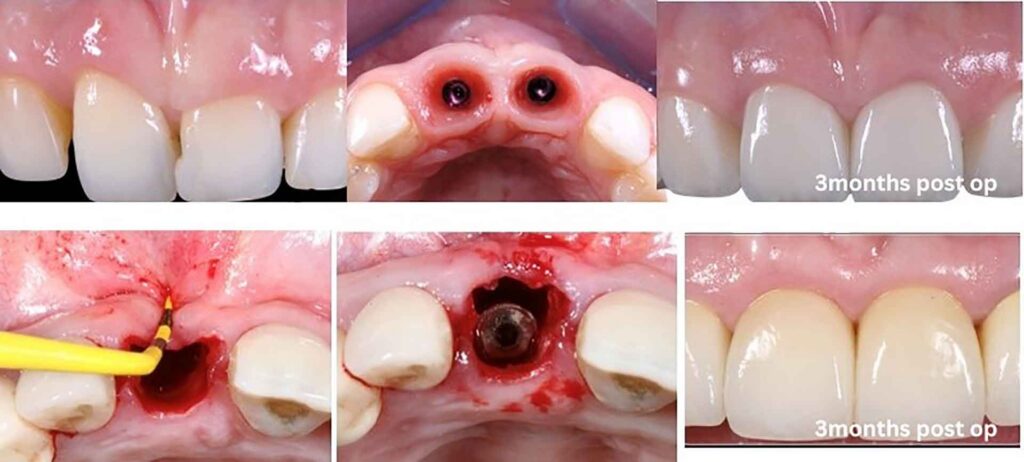

3months post op

Surgical Protocol: Step by Step

While the nuances of patient selection, socket assessment, and digital planning are covered in depth during the IDEA course, the IDR protocol follows a logical sequence that becomes reproducible with hands-on training:

1. Pre-Surgical Assessment and Digital Planning

CBCT evaluation guides implant diameter selection — a paradigm shift from conventional thinking, as IDR uses the fresh socket anatomy differently than traditional protocols. Digital workflow integration allows virtual implant positioning, smile design preview, and fabrication of a provisional prosthesis before the surgery begins.

2. Atraumatic Extraction with Tissue Preservation

Periotomes, thin-bladed luxators, and rotational forces minimize trauma to the alveolar housing. The periosteum is left intact. No flap is raised. This flapless approach preserves the blood supply to the crestal bone — a critical factor in maintaining the buccal plate that is so often sacrificed in conventional extractions.

3. Socket Debridement and Implant Placement

After thorough curettage of granulation tissue and any infected material, the implant is placed with precise three-dimensional positioning. Tapered, deep-threaded implants with moderately to highly roughened surfaces are preferred to maximize primary stability in the incompletely healed socket environment.

4. Maxillary Tuberosity Harvest

Under local anesthesia, a minimally invasive approach exposes the tuberosity. Cortico-cancellous block, particulate cancellous bone, and connective tissue are harvested as the Triple Graft. The harvest site heals uneventfully and patients typically report minimal discomfort beyond the implant site itself.

5. Flapless Bone Reconstruction

The autogenous graft is packed into the gap between implant and socket walls, filling bony deficiencies and establishing a biological seal. Unlike membrane-covered grafting approaches that require a second surgery for membrane removal, the flapless IDR approach leaves the periosteum undisturbed, maintaining vascular continuity and greatly simplifying the post-operative course.

6. Emergence Profile Design and Provisional Restoration

A screw-retained provisional crown is placed at the time of surgery, restoring esthetics immediately and shaping the soft tissue emergence profile from day one. The provisional must be out of occlusal contact during the healing phase, but its presence guides the peri-implant gingival architecture toward the desired final form.